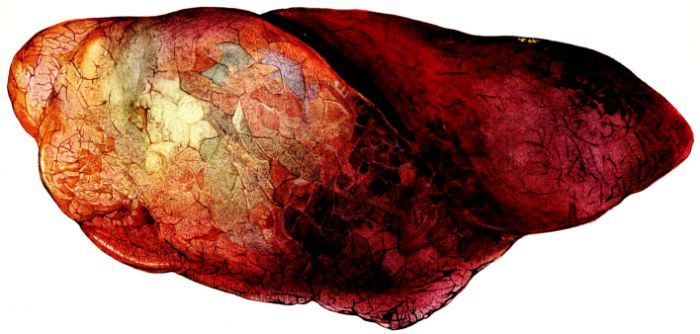

FIG. XIII. AUTOPSY NO. 96. RIGHT LUNG. A WATER COLOR DRAWING OF A GROSS LUNG IN THE ACUTE STAGE. NOTE THE SIZE OF THE LUNG, THE HEMORRHAGES ON THE PLEURAL SURFACE, AND THE BLUE AREAS OF CONSOLIDATION.

19The lungs are extremely voluminous (12, 17) due in part to an accumulation of liquid within them. This finds its way into the trachea and completely fills the latter structure with blood-stained, syrupy fluid, with purulent material, or with a mixture of these (2, 90, 107, 157, 162). At first the pleural surface is smooth and often quite even, but on closer inspection, a minute granulation is suggested. In many cases even close examination does not allow the conclusion that an exudation of anything but serum has occurred through this membrane, except in localized foci. These foci more frequently involve the interlobar pleura and that of the lower lobes (112, 143). The volume of the lungs, often great enough to obliterate the pericardial area, is one of the two most characteristic features of the external examination. The other feature is their color. Small, bright red hemorrhages may occur anywhere. The larger patches are the most striking. Violet, purple, or dark brown areas, irregular in shape and distribution, are more frequently found on that portion of the pleura over the lower two-thirds of the lung. Between the deeply colored zones, there are pale pink areas which involve the lowermost edge to the least degree, the anterior margin somewhat more, and the apex of the lung most of all. The darker portions just referred to may project above the surface and may be circumscribed, resembling huge, fresh hemorrhagic infarcts (41, 108). The alveolar walls are not seen through the pleural surfaces in these darker zones. The pale pink areas, usually at the level of the more intensely colored zones, may be elevated and the dilated air sacs are distinctly made out through the pleura (Fig. XIII). At the hilum, the lymph glands are large and soft. When cut, fluid escapes and is often blood-stained. The cross section may present a distinct, diffuse, hemorrhagic appearance (162). At the hilus, too, the lymphatics, distended here and there over the surface of the pleura, are most affected. The congested bronchial mucous membrane and the exudate in these structures has been described.

After removal, the lung retains its shape, but is more flaccid than the consolidated lung of lobar pneumonia. It cuts with very little resistance and immediately a large amount of a syrupy, pink fluid escapes and obscures the entire area. With the fluid scraped away, the variations in the consistency of the lung become visible. The pale areas around the borders and chiefly at the apex in which the air sacs are discernible with the naked eye, sink slightly below the remainder of the surface, and the pleural edge inverts. The individual lobules of the lung in these areas are more conspicuous than normal, because the interstitial tissue bearing the lymphatics and vessels, as well as that around the bronchi and larger blood vessels, does not lose its edematous appearance as quickly as the alveoli (40, 92, 110, 164), and, consequently, these grey lines and points stand up somewhat more prominently.[6] In contrast with the paler areas which are prone to slight collapse, the remainder of the cross section retains its more smooth and even surface. The alveolar walls are not distinctly made out, but the terminal bronchioles often make themselves evident by the nature of the material which is within and by their distinct dilatation (1, 67, 110, 149, 162). The more firm areas stand out, too, on account of their difference in color. The scheme is not unlike that seen on the pleural surface, and while dark, almost black, infarct-like areas occur on the cut surface, the solid areas are more likely to be translucent, dull, light red, brown or even grey. They have a surface similar to a very fresh, tuberculous, gelatinous pneumonia, but the color differs from the cloudy grey of the latter on account of the admixture of blood in the exudate and the great congestion of the vessels (Fig. XIV).

The well developed post-mortem muscular rigidity, the lividity of the dependent parts, of the face with its mucous membranes, and often of the trunk, the jaundice variable in extent, the crusts of blood on the nares and mouth, and the splanchnic dilatation are features which prepare for the gross picture presented by the thoracic organs. The increased moisture within the pleural cavities associated with the even, translucent pleural surface, whose dilated lymphatics become more and more prominent towards the hilum, the large succulent lymph glands, and the exudate in the bronchial tree, are all striking, but more characteristic of the gross picture, is the great increase in volume of the lung itself, mottled 20with brilliant colors. The lung, too, is very wet and on section, after the syrupy, blood-stained fluid escapes from the less definitely consolidated zones, the latter appear, not as the usual granular, firm areas of hepatization, but have more the consistency of a gel, and also its translucence. Characteristic of this disease as these changes may be, the specificity of the fundamental lesion in the respiratory tract, becomes more emphatic after study of its histology (92, 162).